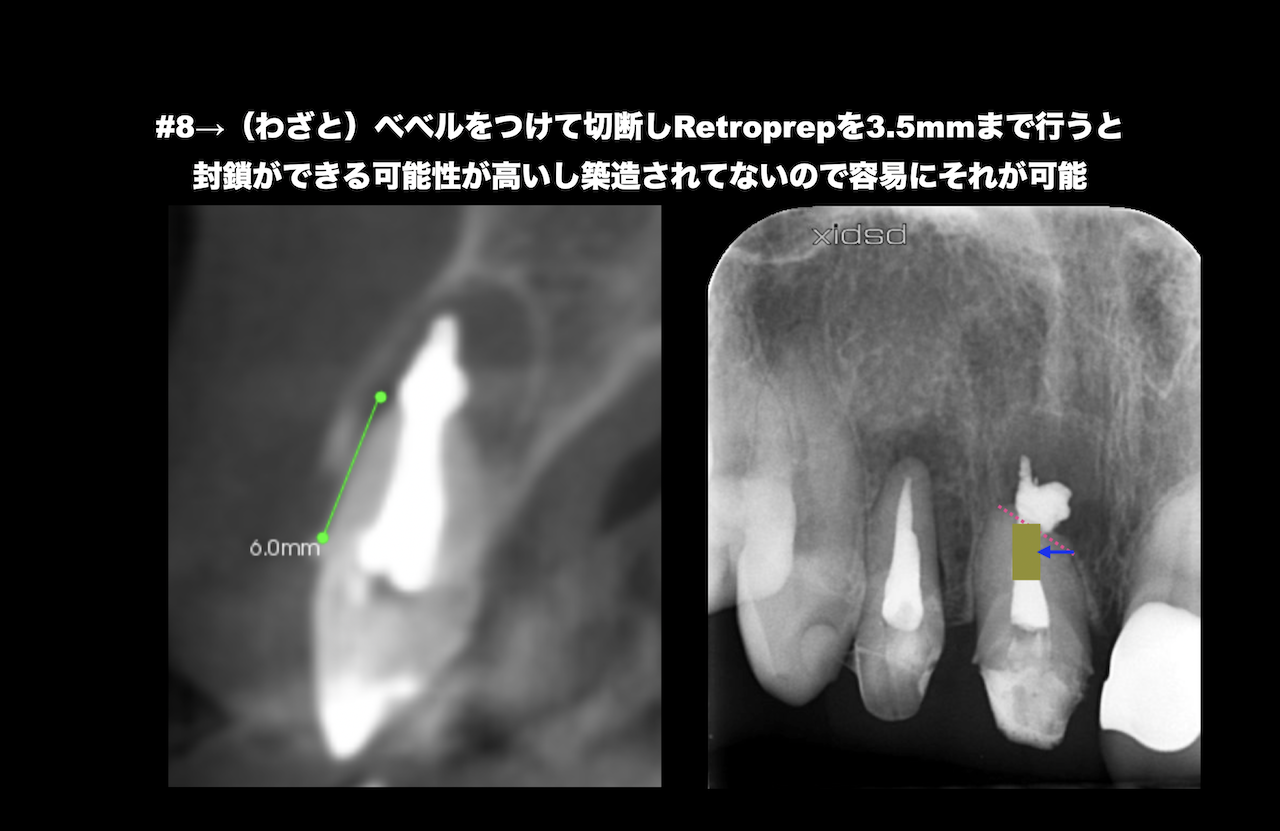

最後にIntentional Replantationが困難な歯に対するApicoectomyについて解説した。